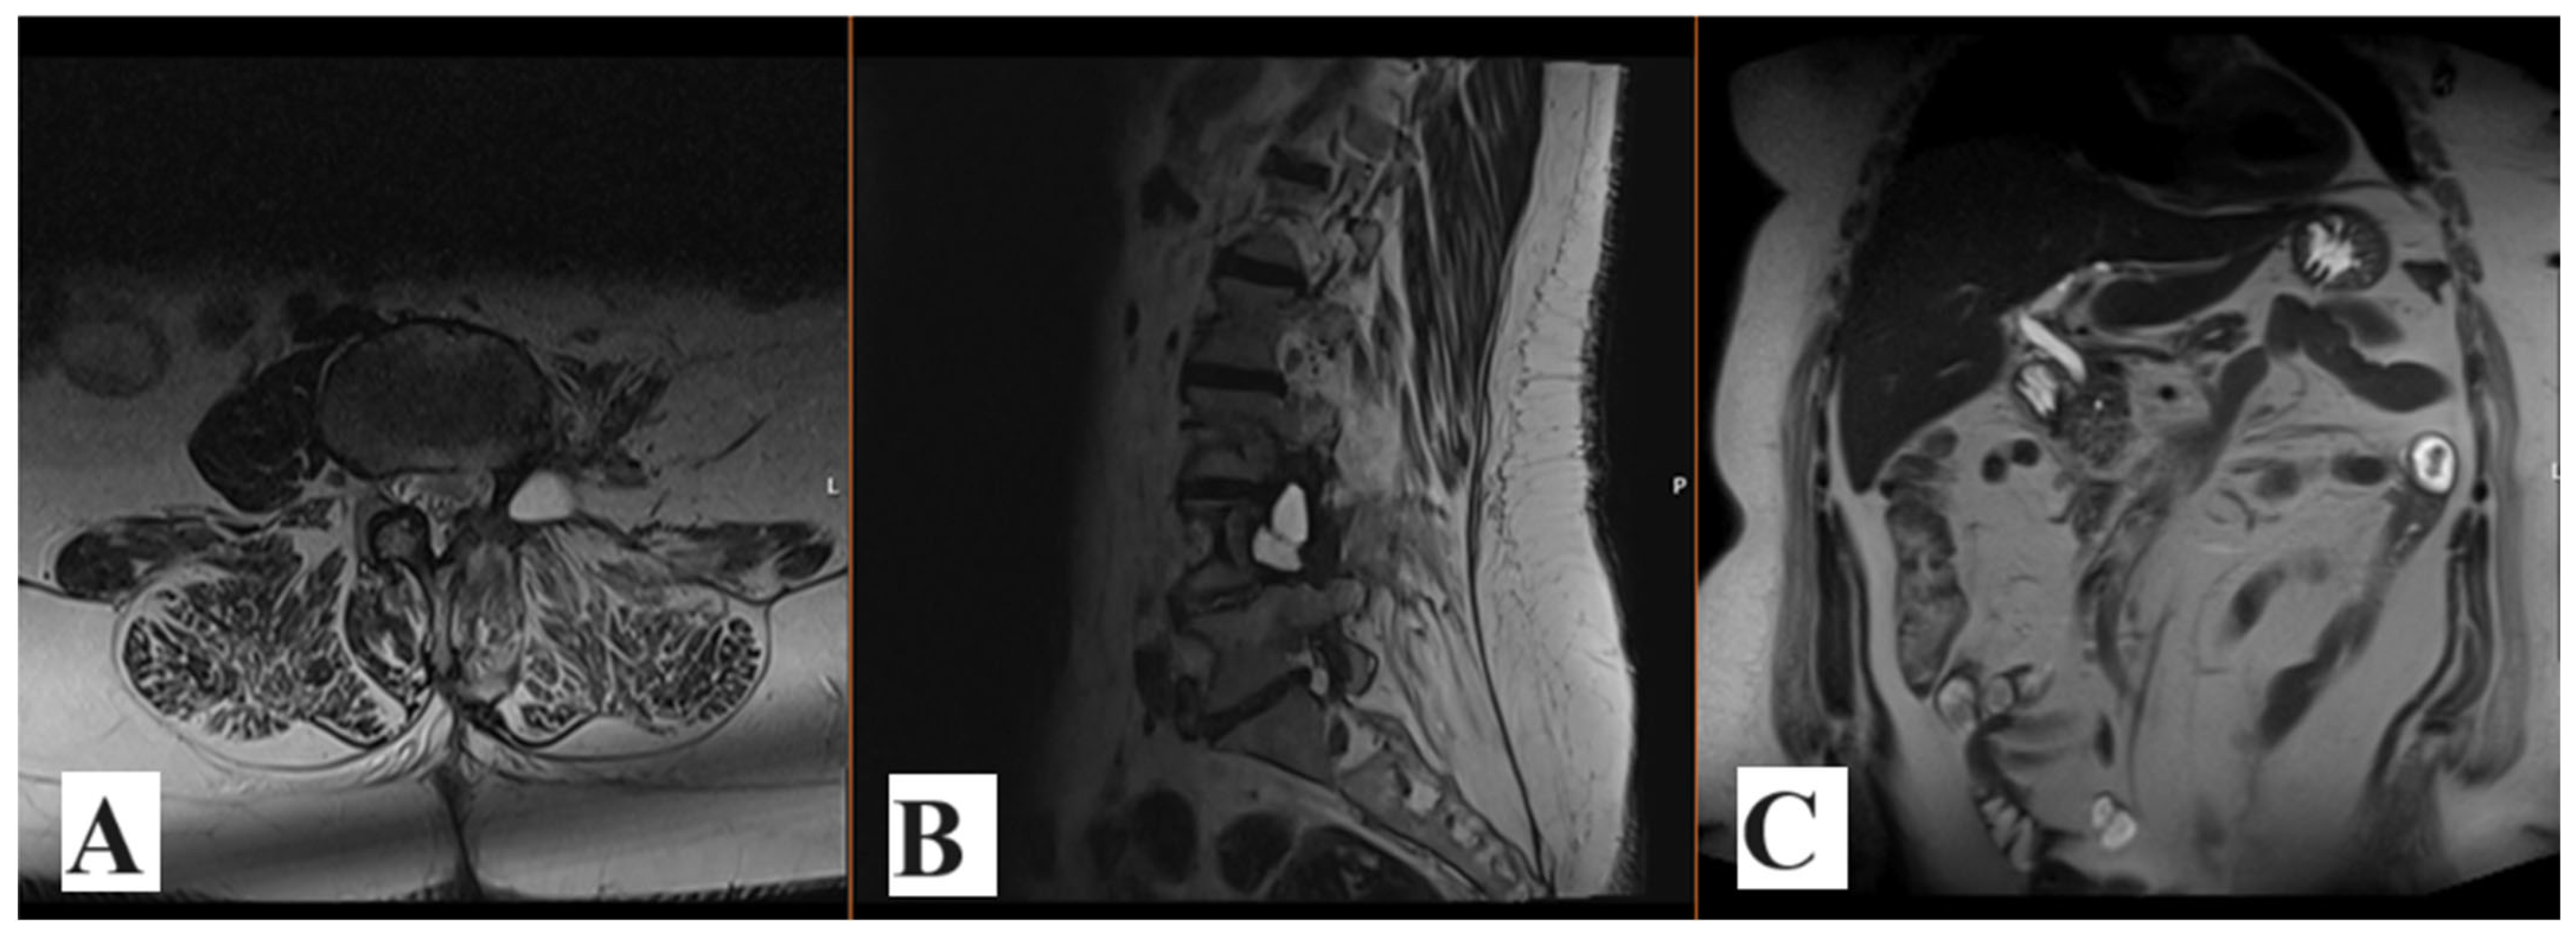

2. Case Report